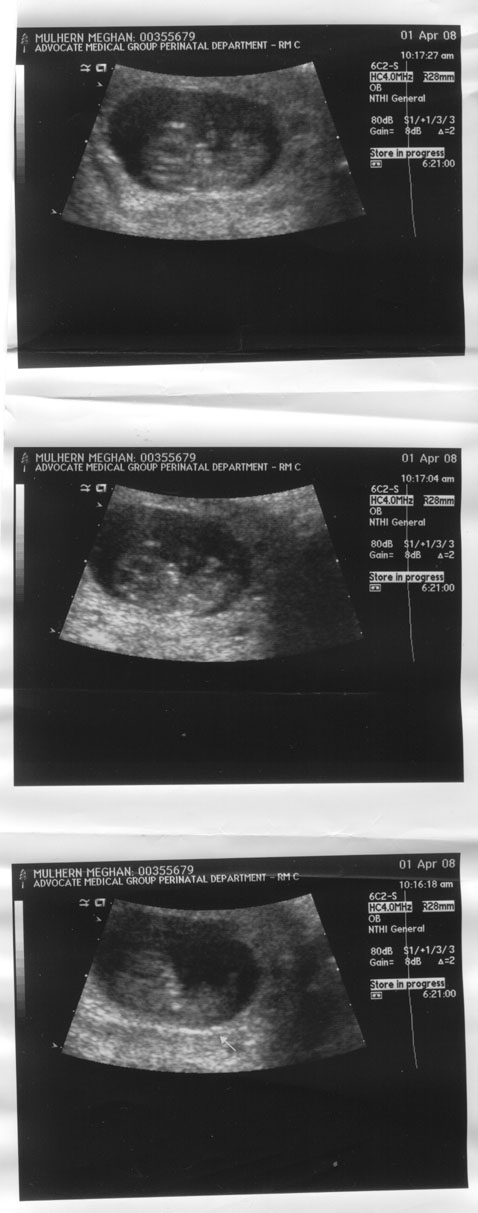

9 Week Ultrasound